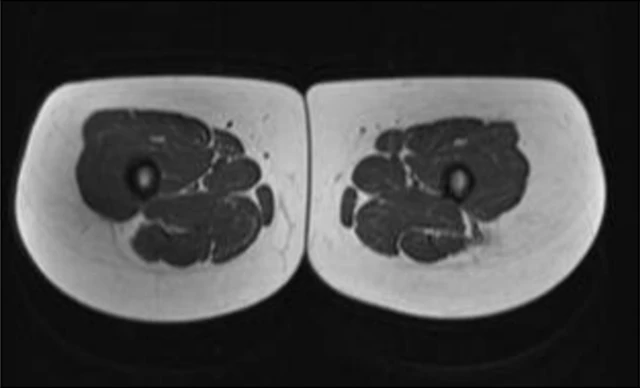

Vergleich des Oberschenkelquerschnitts eines 21-jährigen und eines 83-jährigen – weiss ist Fettgewebe

(Quelle:  published online on 01.11.2019, https://doi.org/10.34045/SSEM/2014/25)

Vergleich des Oberschenkelquerschnitts eines Fettleibigen und Normalgewichtigen